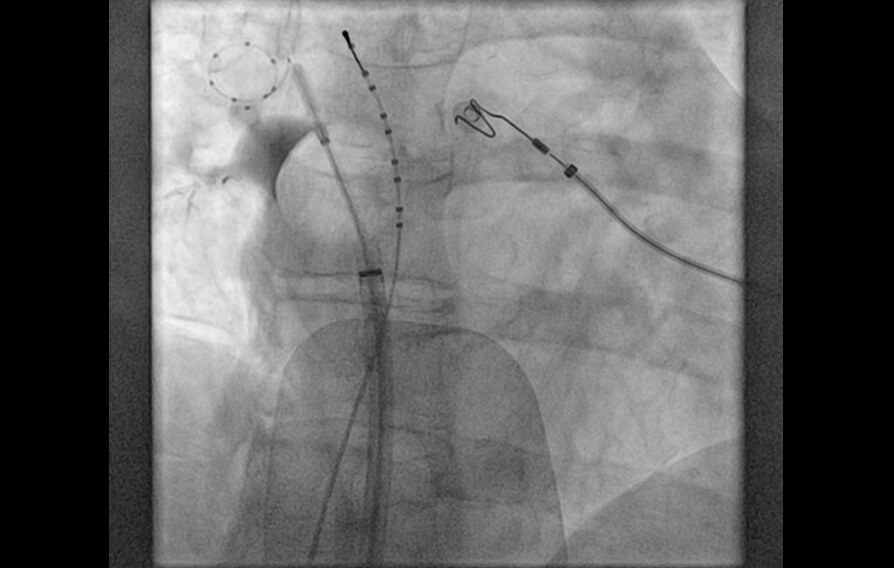

El tratamiento por cateterismo de las arritmias suele realizarse con la aplicación de calor que elimina el foco que produce la arritmia. La crioablación, por el contrario, aplica frío para congelar el foco arritmogénico. La aplicación de frío es más segura y previene lesiones irreversibles. Gracias a esta tecnología, podemos tratar con seguridad arritmias localizadas en zonas del corazón muy cercanas a estructuras importantes que de otro modo tendrían riesgo de ser dañadas.